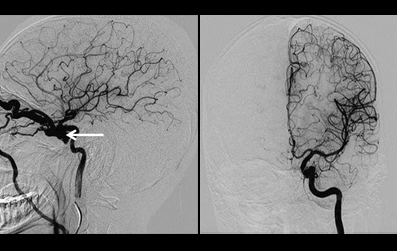

Figure 3: DSA of left ICA showing dilated, tortuous superior ophthalmic vein draining into prominent facial vein. DSA of left ICA after 2 weeks showing that carotid-cavernous fistula no more visible and no prominent veins in arterial phase in lateral view. (Page 20)